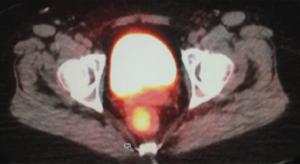

A 56-year-old Caucasian woman presented to her primary care physician with a 3-month history of intermittent bright red rectal blood with defecation. At her initial visit, a digital rectal examination, anoscopy, and a pelvic examination with DNA testing for high-risk HPV were performed; all results were negative. She was referred for a colonoscopy, which revealed an abnormal area with a 3 × 4–cm mass in the rectum at a distance of 10 cm from the anal verge.